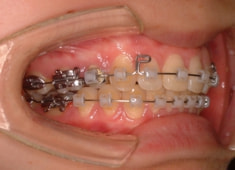

治療開始から1年7ヶ月後